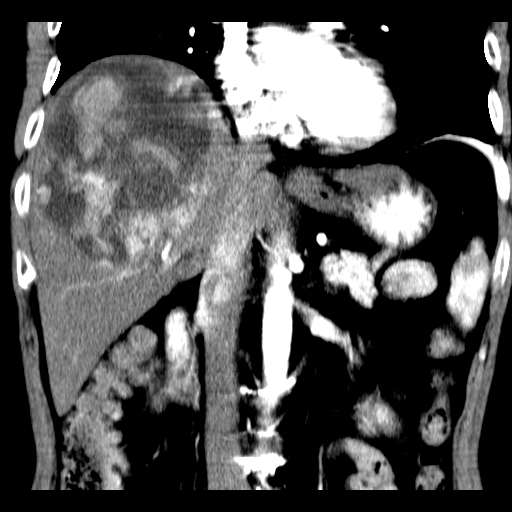

以下是引用卜一在2008-6-23 15:38:00的发言:[br]本例延时期的图象未扫完,单纯平扫 动脉期及门脉期特征分析:平扫低密度较大肿块,内见不规则出血灶,界限清楚。动脉期边缘结节样强化,门脉期病灶边缘进一步强化并范围明显缩小。因此考虑:血管瘤伴出血!

以下是引用深泽交通医院在2008-6-23 16:40:00的发言:[br]考虑肝癌伴出血.诊断依据:平扫瘤壁结节密度低于肝实质,动脉期壁结节明显强化,门脉期略低于肝实质密度[br]病灶有明显的假包膜,